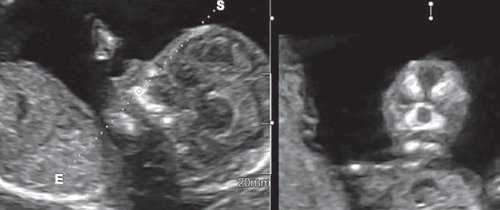

Clinica lаs Condes, Santiago, Chili.

Важнейшим маркером генетических синдромов как хромосомного, так и нехромосомного генеза, является микрогнатия. Микрогнатия (нижняя микрогнатия, микрогения) - аномалия развития нижней челюсти, характеризующаяся ее гипоплазией. Диагностика этого состояния при трисомии 18 и триплоидии доходит до 80% [1, 2]. При введении в поисковую систему OMIM термина "micrognatia" можно встретить 447 различных синдромов и ассоциаций, в синдромальное ядро которых входит этот важный генетический маркер. Одна из самых крупных работ в мире по изучению этого маркера принадлежит D. Paladini и соавт. [3], которые описали более 50 случаев микрогнатии в сочетании как с хромосомными [4], так и нехромосомными синдромами и ассоциациями. Степени микрогнатии рассматривались от крайней - агнатии, входящей в состав аутосомно-рецессивного синдрома агнатии, голопрозэнцефалии (отоцефалии) [5, 6]. Отоцефалия - чрезвычайно редкая аномалия, при которой встречаются грубые лицевые дизморфии: недоразвитие или тяжелая гипоплазия нижней челюсти, неправильное положение ушей (рис. 1, 2), которые могут быть объединены и чаще всего располагаются на шее плода [7]. Также крайне выраженная степень микрогнатии может встречаться при окуло-ауриколофронтоназальном синдроме. Он был выделен в самостоятельную нозологическую группу, объединяющую симптомы как фронтоназальной дисплазии, так и синдрома Гольденхара [8, 9].

Рис. 1. Профиль плода с синдромом агнатии-голопрозэнцефалии в 12 нед беременности.

Рис. 2. Фенотип лица плода при синдроме агнатииголопрозэнцефалии в 12 нед беременности.